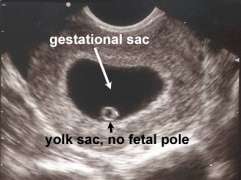

Gestational sac greater than 18mm without fetal pole Collapsed gestational sac

- Gestational sac >10mm without visible yolk sac

- Gestational sac >18mm without fetal pole